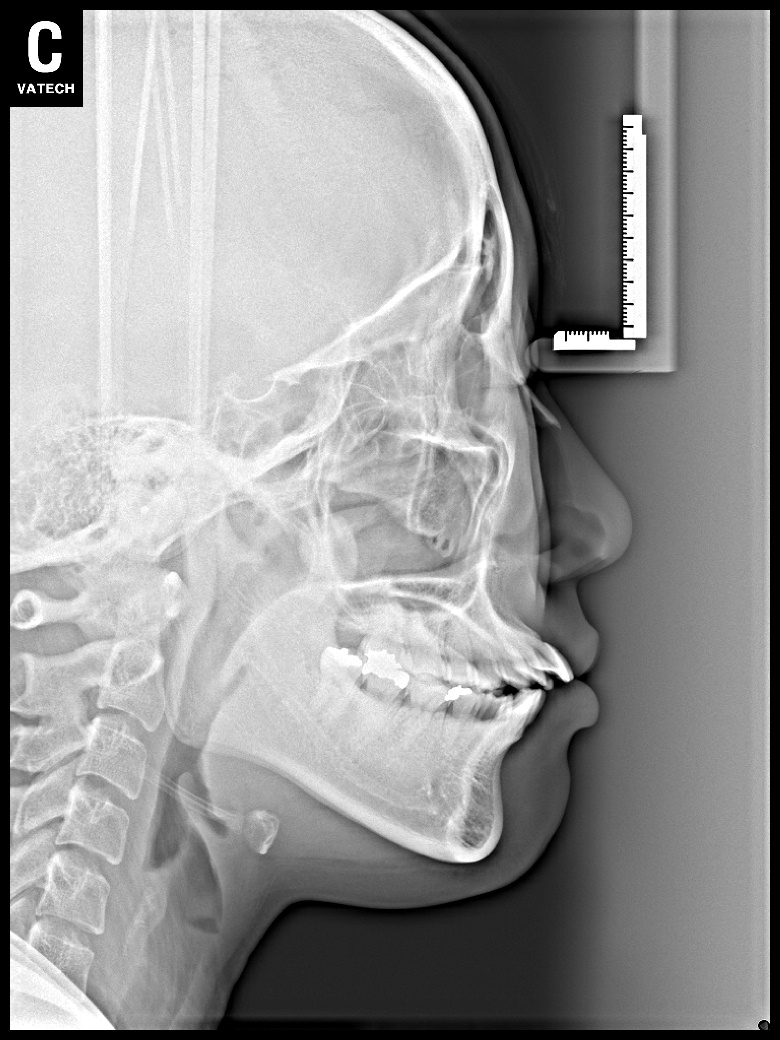

치료 전 사진입니다.